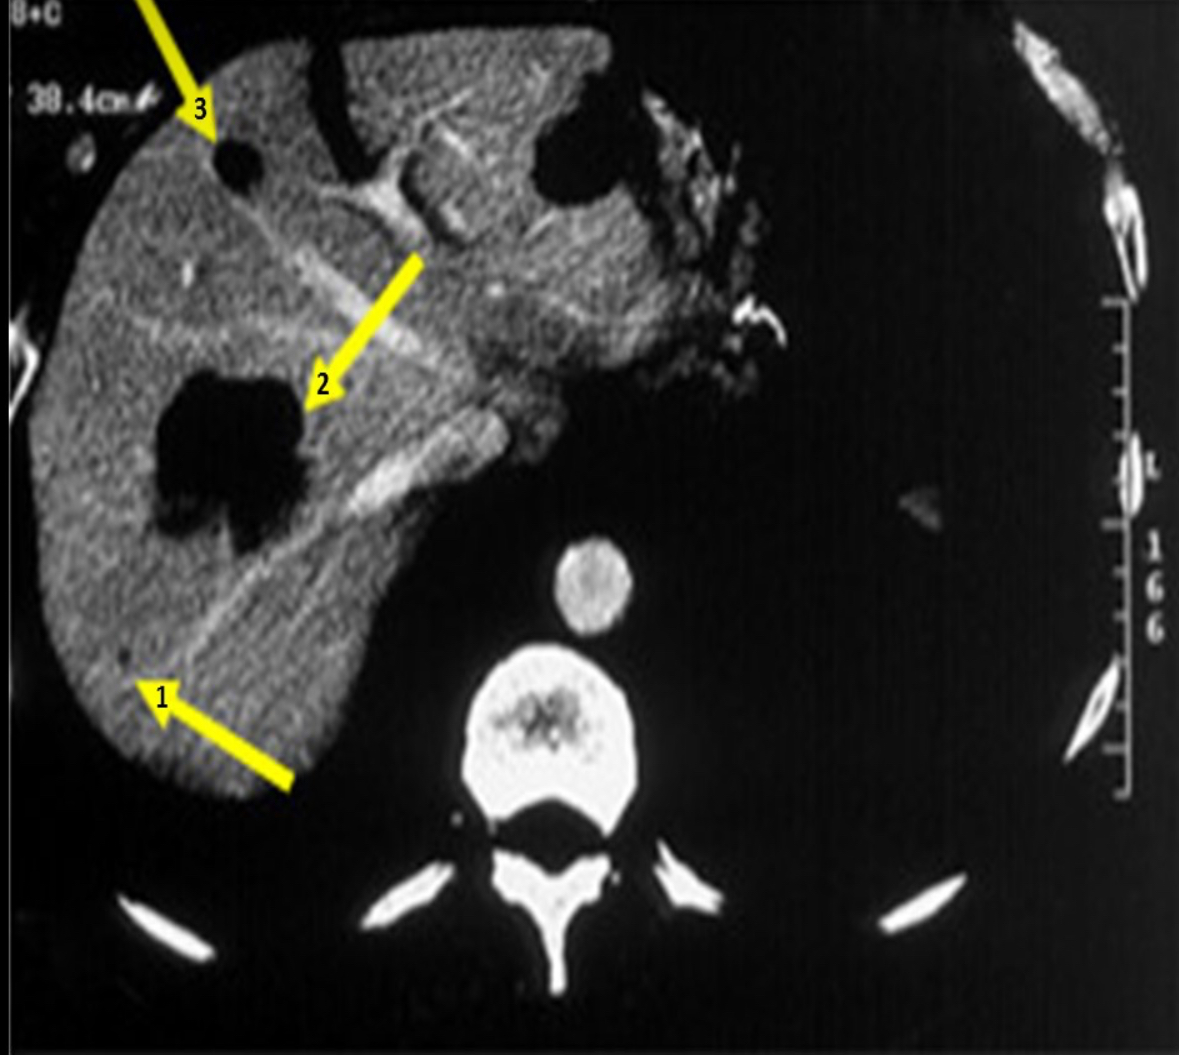

A patient is referred for an abdominal ultrasound due to abnormal CT scan. Refer to the image to determine where will you find the mass marked with #3?

Left medial superior segment

a patient is referred for an abdominal ultrasound due to an abnormal CT scan referred to the image to determine where you’ll find the largest liver mass.

Right anterior superior segment

A patient is referred for an abdominal ultrasound due to an abnormal CT scan. The yellow arrow indicates the gallbladder. Based on the single CT image, which of the following is expected finding on the ultrasound evaluation.

gallbladder wall thickness >3 mm